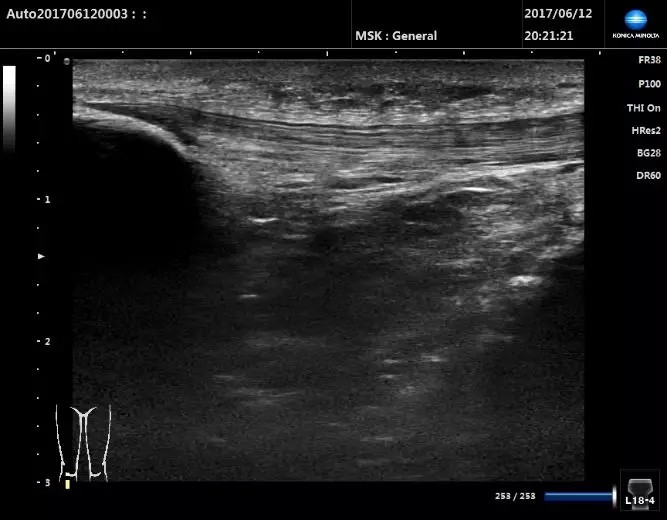

超聲掃查髕腱

探頭放置在髕骨下方,矢狀切面顯示成纖維狀高回聲的髕腱。